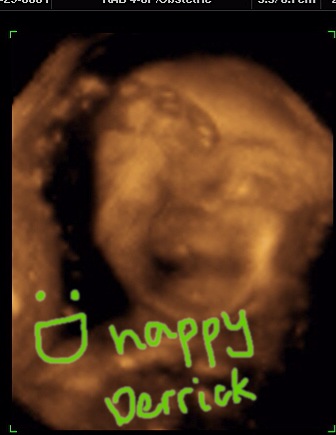

Al actually started with a regular 2D, found where the face was, and converted the image to 3D! WOW... technology amazes me! And Derrick, oh Derrick, he is such a happy baby. He has a smiling face, and he was so active with his body and also with his face, even Al said he might talk faster because he's moving his lips so much already!

Here he is

He's so beautiful, isn't he?

Here he is smiling again, he has his daddy's nose and mommy's mouth :] And saluting us with his hand! (upper left corner)